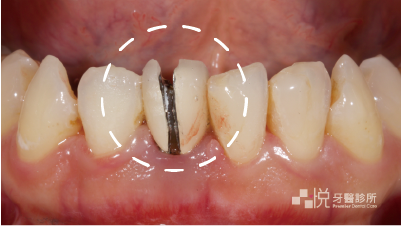

馬利蘭牙橋黏著上去以後,誒?怎麼感覺好像還差了一點點?

原來是阿婷看了看鏡子,覺得黑三角縫的部分太大了。

沒關係,我們藉由美學樹脂填補的方式,不只縮小了黑三角縫,也修正了舊有填補物顏色稍為沒那麼理想的小缺憾。

治療完成後我再三叮嚀阿婷後續要定期半年按時回來檢查追蹤,然後也要存錢準備矯正了。雖然我這樣一直碎唸他應該覺得很囉唆,但是忠言逆耳是真的,希望這次他是真的有聽進去 😂